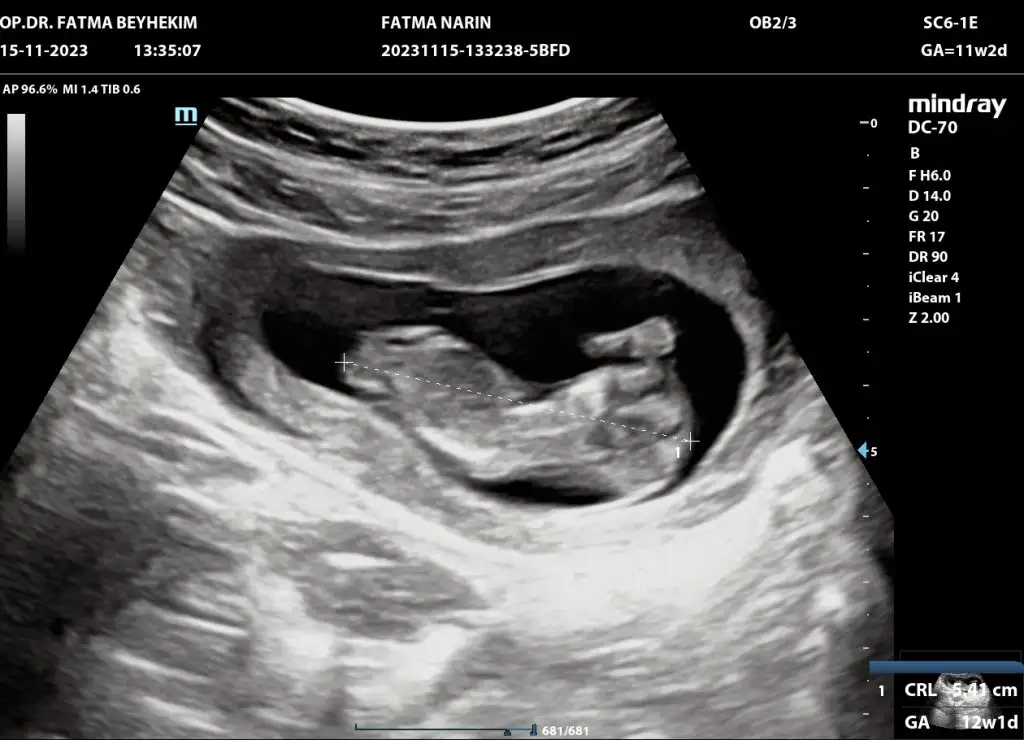

Merhaba erkek gibi benim ultrasonuda yorumlarmisiniz acaba

Eklentiler

• IMG-20240308-WA0003.webp

IMG-20240308-WA0003.webp

12,2 KB · Görüntüleme: 60

Arkadaşlar merhaba daha önce burada ultrason fotoğrafına bakıp cinsiyet tahmin edenleri görmüştüm benim içinde bi heyecan olur:) var mıdır tahmininiz normalde 12+4 üm ama ultrasonda 13 haftalık görünüyor

Erkek gibi hayırlı olsun benim ultrasonda yorumlayacak birisi varımdır acaba